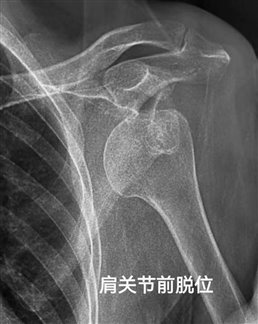

肩关节是人体活动范围最大的关节,由肱骨头、肩胛骨关节盂及周围韧带、肌腱组成。当外力导致肱骨头脱离关节盂的正常位置时,就称为肩关节脱位,根据脱位方向可分为前脱位、后脱位、下脱位,其中前脱位占95%以上(常见于摔倒时手掌撑地、肩关节外展外旋发力)。

3.外观畸形:肩关节明显肿胀、变形,对比健侧肩膀,会发现受伤侧肩膀“变平”(失去正常圆润轮廓),或出现“方肩”畸形(肱骨头脱出导致);

3.尽快就医:不要拖延,及时前往医院急诊科,通过X线检查明确脱位类型,排除合并骨折(如肱骨大结节骨折),由专业医生进行复位。